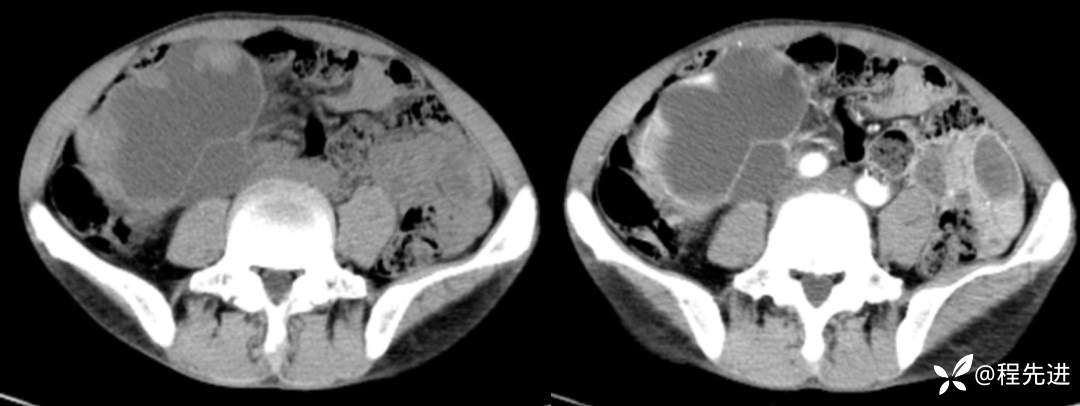

CT平扫+增强

左平扫,右增强